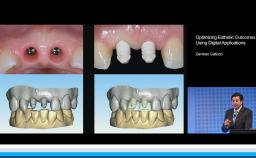

German Gallucci

Boston, United States